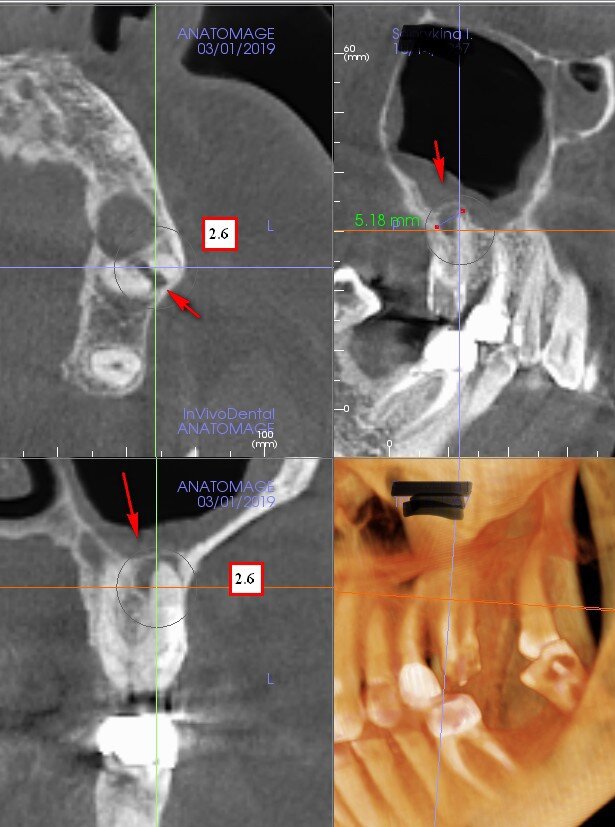

Очень часто пациент лечит одонтогенный синусит антибактериальной терапией и другими способами толку от которых ноль. Почему? Всё просто причиной воспаления в пазухе является зуб, именно через него проникают бактерии и устраивают полное безобразие в пазухе! Пациент может годами мучится проколами и пичкать себя антибиотиками со слабым временным эффектом, но как только причинный зуб удаляют, жизнь начинает играть новыми красками! Так что если у вас при снижении иммунитета начинается односторонний синусит, посетите врача хирурга-стоматолога, лишним не будет!